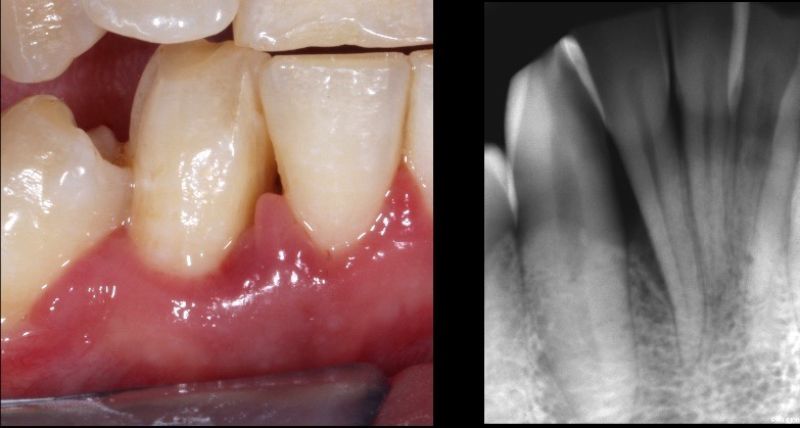

A deep intrabony defect treated with Straumann® Emdogain® – 10-year follow-up of a clinical case

I started to use Straumann® Emdogain® in 2006 during my postgraduate education. Since then, the main indications for which I utilize Straumann® Emdogain® are intrabony defects and furcation defects, alone or in combination with grafting materials. I also use it regularly in my mucogingival surgeries. Recently, I have also been using Straumann® Emdogain® FL applied non-surgically in flapless periodontal procedures. Overall, I can say that Emdogain® is a unique biological material that enables real periodontal regeneration by supporting the development of new cementum. In addition, it has allowed me to obtain good results in early wound healing.

Based on a correct indication for periodontal regenerative treatments, Straumann® Emdogain® removes the complexity of grafting procedures and reduces the risk of wound healing complications. On the other hand, Straumann® Emdogain® provides a real regeneration by precipitating on the root surface to form a matrix that bio-stimulates and promotes the formation of new cementum.